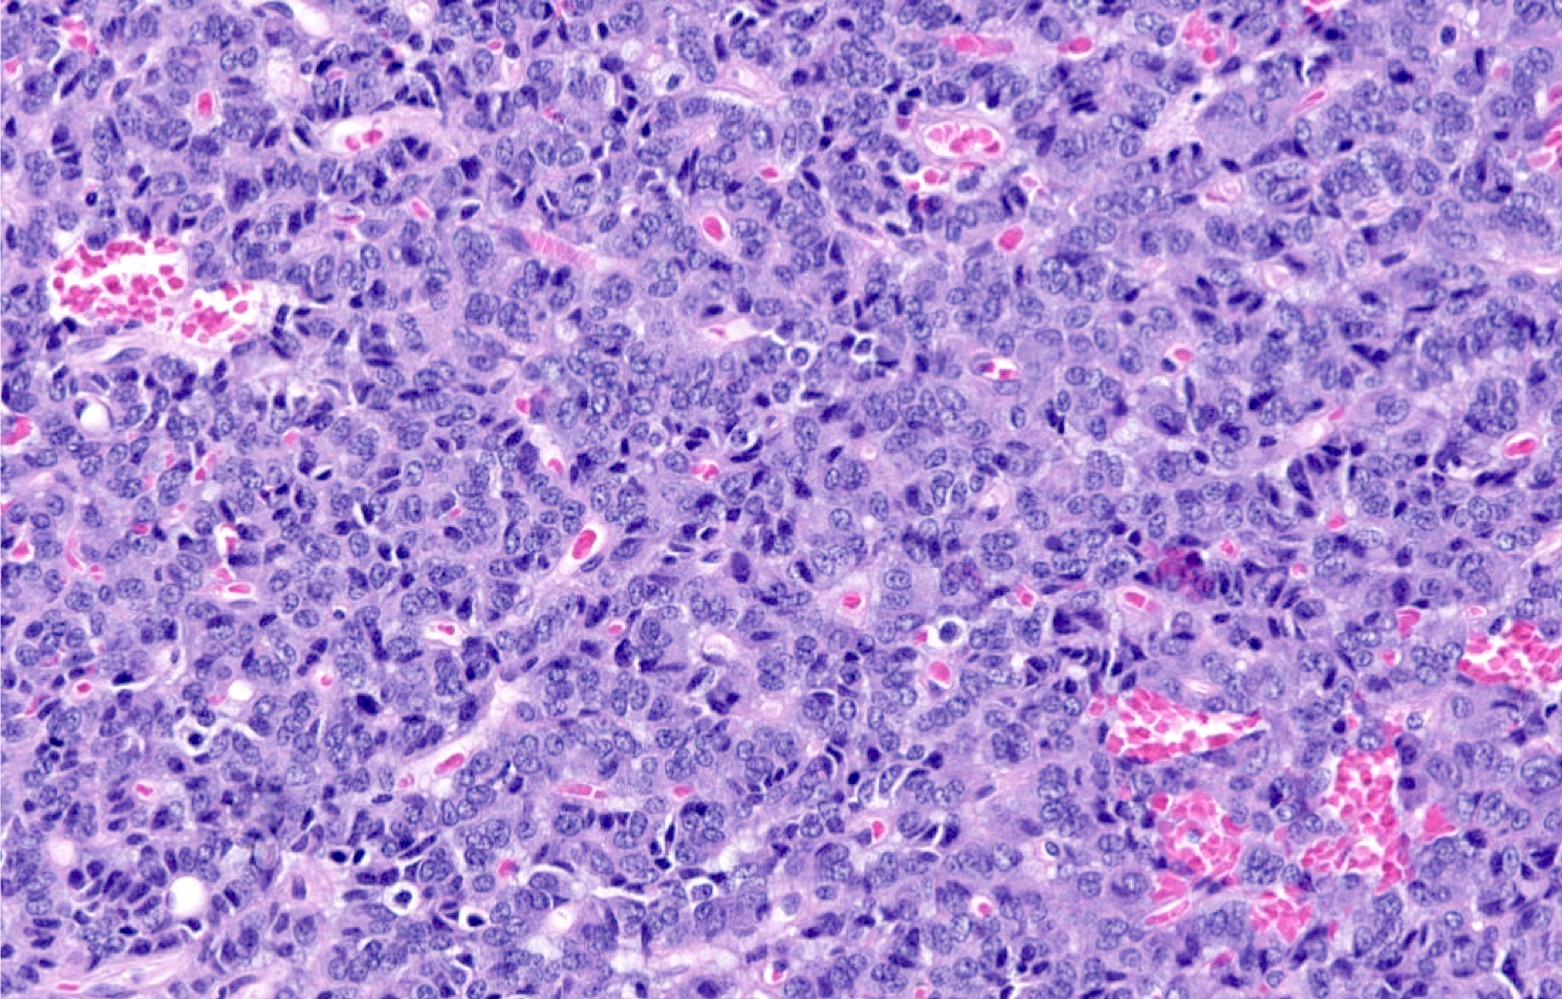

Microscopic (histologic) description

- Diagnostic criteria

- Neuroendocrine tumor with size ≥ 5 mm with < 2 mitoses/2 mm2 and absence of necrosis

- Neuroendocrine growth pattern (organoid, trabecular, rosette formation, nested) or pseudoglandular, follicular and papillary growth

- Tumor cells are uniform with a polygonal shape, round to oval nuclei with salt and pepper chromatin as well as inconspicuous nucleoli and moderate to abundant eosinophilic cytoplasm

- Spindle cells and clear cell features can be seen

- Stroma is fine and highly vascularized; hyalinization, cartilage or bone formation are possible

- Reference: Curr Oncol 2018;25:S86

Microscopic (histologic) images

Contributed by Philippe Joubert, M.D., Ph.D., Jijgee Munkhdelger, M.D., Ph.D. and Andrey Bychkov, M.D., Ph.D.

A 55 year old woman had a lower left lobectomy showing a well circumscribed flesh colored tumor. Histologic details are shown in the image above. Regarding this entity, which of the following statements is true?

A. CDX2 is usually negative in the lung and is useful to differentiate from a metastasis of an intestinal origin. The image shows a tumor with a trabecular pattern and pseudorosettes. The stroma is highly vascularized. Tumor cells are monotonous with scant to moderate eosinophilic cytoplasm. Nuclei are round to oval with salt and pepper chromatin and inconspicuous nucleoli. No mitoses are seen. These features are consistent with a typical carcinoid lung tumor.